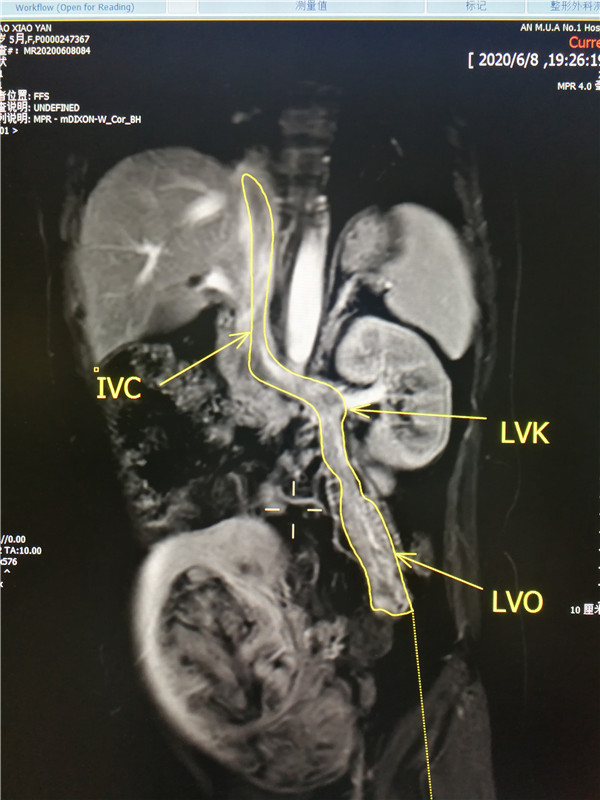

心脏大血管外科分享患者临床资料,以及国内外针对这一疾病的治疗方式、手术录像。影像科、B超室、心超室专家详细分析患者影像学资料,明确患者肿瘤起源于子宫,经卵巢静脉、左肾静脉、下腔静脉,一直长至右心房内,形成鸡蛋般大小的心房肿瘤;肿瘤大部分与静脉壁无明显粘连,但左肾静脉等处有轻度粘连,加大了肿瘤完整取出的难度。妇科专家提出,患者肿瘤起源于子宫,子宫肌瘤直径达17cm,必须要将肿瘤连根拔起、彻底清除,防止未来复发。肝胆外科专家指出,患者平滑肌瘤几乎占满整段下腔静脉,肝脏附近的下腔静脉内肿瘤如果粘连明显,必要时可切开肝后下腔静脉取出。泌尿外科专家提示,手术中需要游离好左肾静脉及附近血管,充分做好完整取出肿瘤的准备......经历多次会诊,多学科共同参与、精心设计,最终决定只用一次手术,为邵女士彻底切除肿瘤!